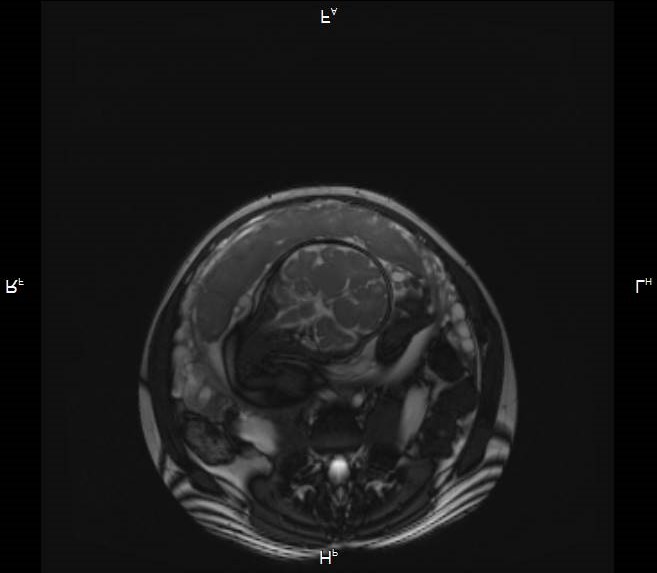

Первичный, или «материнский» этап, длительностью 3–5 минут, при котором получаемые Т2-ВИ многоплоскостные ортогональные МР-изображения (рисунок 1) ориентируются согласно анатомии беременной; целью его является оценка сегментарного расположения плацентарного диска в полости матки, контуров и размеров матки.

|

|

|

| А | Б | В |

| Рисунок 1 – Беременность 36 нед. МРТ плаценты. Первичный, «материнский» этап исследования. Т2 ВИ в сагиттальной (а), корональной (б) и аксиальной (в) плоскостях | ||

Завершающий, или «тазовый» этап, длительностью не более 5–10 мин, при котором прицельно оценивается нижние сегменты матки, внутренний зев, шейка матки, мочевой пузырь, смежные ткани и органы таза беременной с целью выявления критериев прорастания плаценты, которые могут соответствовать 3 (a, b, c) степени согласно классификации FIGO (2018) для клинической диагностики группы плацентарных нарушений адгезивно-инвазивного спектра (рисунок 2).

|

||

| а. | ||

|

|

|

| б. | в. | г. |

| Рисунок 2 – Беременность 36 нед. МРТ плаценты. Основной, «плацентарный» этап исследования. Варианты позиционирования срезов для получения ортогональных изображений плаценты в косо-сагиттальной (б), косо-корональной (в) и косо-аксиальной (г) плоскостях относительно анатомии беременной по МР-изображениям первичного этапа (а) | ||